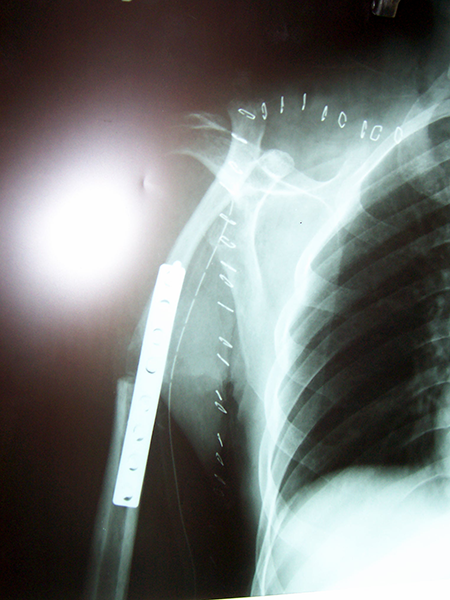

Case:6 Transfer of Scapula to Humerus

Pre-Op X-ray

Post Fixation

Post-op X-ray